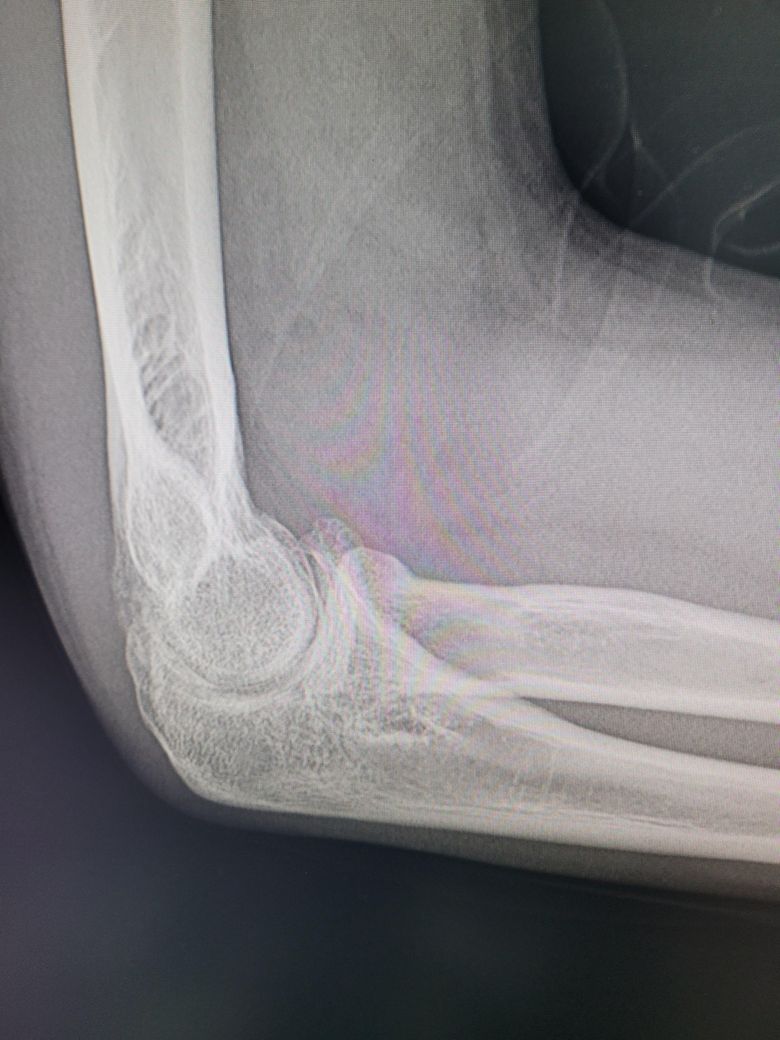

팔이 아파서 여러병원 찾아다니느라 엑스레이 사진도 복사해왔는데 1,2년 전에 비해서 팔꿈치에 동그란 게 생겼더라구여 이게 뭔지 모르겠습니다

과거에 활액막연골종으로 같은 부위를 수술받은 적이 있습니다

첫 번째 두 번째 사진이 가장 최근입니다

• 1번 째 사진